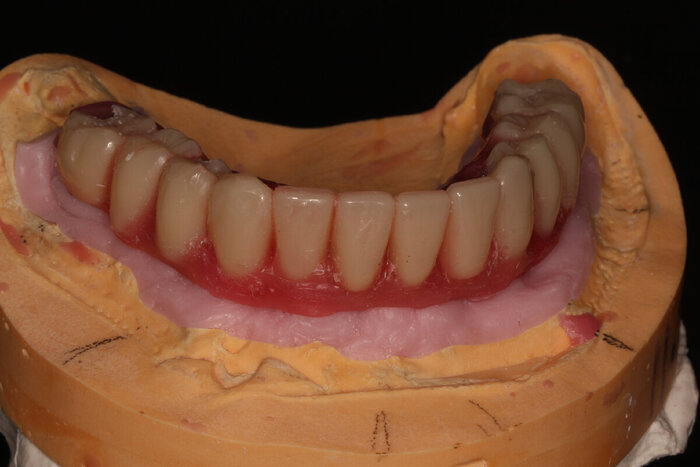

Пока верх не закончен, можно переходить к низу. Тут всё проще (как это часто и бывает). Выбор сделан в пользу тотальной работы на 6 имплантатах (сверху, по итогу, будет то же самое).

Мы распечатали шаблоны, которые помогал проектировать зубной техник Михаил:

Напомню, что шаблон не один, их много - базис, для сверления и досверливания (2 штуки), постановка и ложка. К базису крепятся составные части магнитами. Хотя, когда случаются особые случаи, всё крепится по-старинке, острыми и длинными "копьями" - пинами.

Протез будет с розовой десной и-за дефицита тканей (FP3).

Посмотрим на восковой протез нижней челюсти поближе.

Временный адаптационный протез с опорой на 6 имплантов.

Временный адаптационный протез с опорой на 6 имплантов

Временный адаптационный протез с опорой на 6 имплантов. Нижняя челюсть.